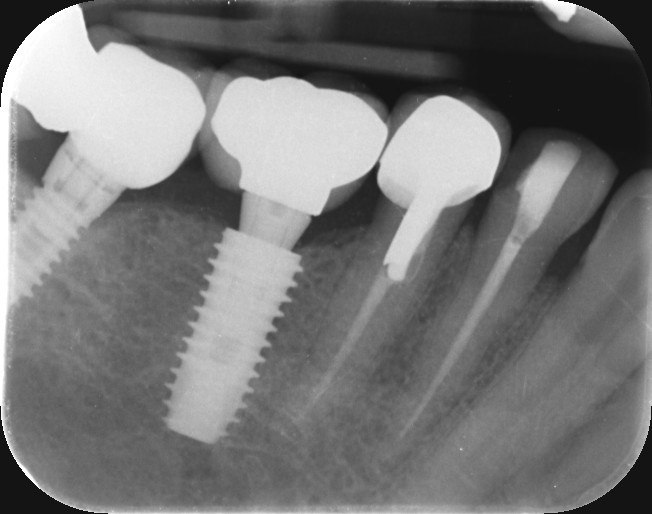

1. What option can be selected regarding the implant seen in this X ray?

2. What option can be selected regarding the implant seen in this X ray?

3. What option can be selected regarding the implant seen in this X ray?

4. What option can be selected regarding the implant seen in this X ray?

5. What option can be selected regarding the implant seen in this X ray?

6. What option can be selected regarding the implant seen in this X ray?

7. What option can be selected regarding the implant seen in this X ray?

8. What option can be selected regarding the implant seen in this X ray?

9. What option can be selected regarding the implants seen in this X ray?

10. What option can be selected regarding the implant seen in this X ray?

11. What option can be selected regarding the implant seen in this X ray?

12. What option can be selected regarding the implants seen in this X ray?

13. What option can be selected regarding the implants seen in this X ray?

14. What option can be selected regarding the implants seen in this X ray?

15. What option can be selected regarding the implants seen in this X ray?

16. What option can be selected regarding the implants seen in this X ray?

17. What option can be selected regarding the implants seen in this X ray?

18. What option can be selected regarding the implants seen in this X ray?

19. What option can be selected regarding the implants seen in this X ray?

20.What option can be selected regarding the implants seen in this X ray?